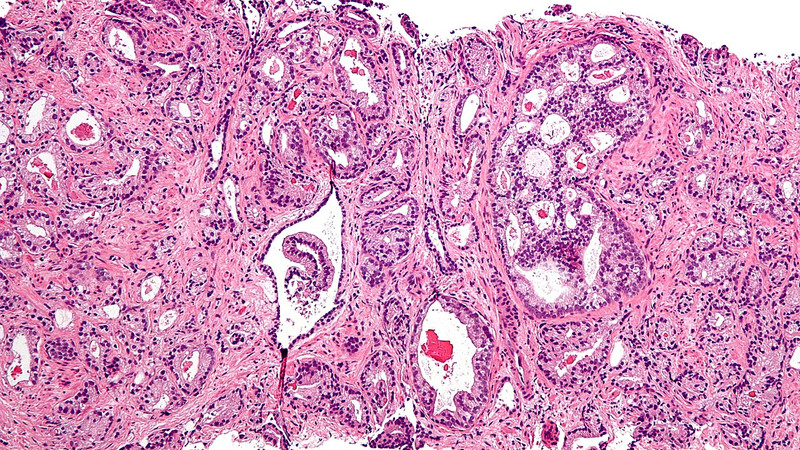

The state of the art imaging test uses a molecule that binds to prostate cancer cells, causing them to “light up in a remarkable way”—appearing as bright spots in the scanning image.

Their PSMA PET/CT scan identifies the more aggressive prostate cancer cells, which are potentially harmful and may need treatment—and could help reduce the risk of over-diagnosis by determining which cancers are low-risk and will never cause harm.